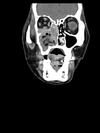

Central skull base Basal cephalocele

FIGURE 31-5 Basal encephalocele.A, A sagittal T1-weighted image shows callosal agenesis with a tiny lipoma (arrow). A large defect in the basisphenoid is seen. Note the apparent absence of the pituitary, floor of the third ventricle, and optic pathways. B, A high-resolution sagittal T2-weighted image shows the pituitary-hypothalamic structures (arrow) and optic pathways are contained within the encephalocele.